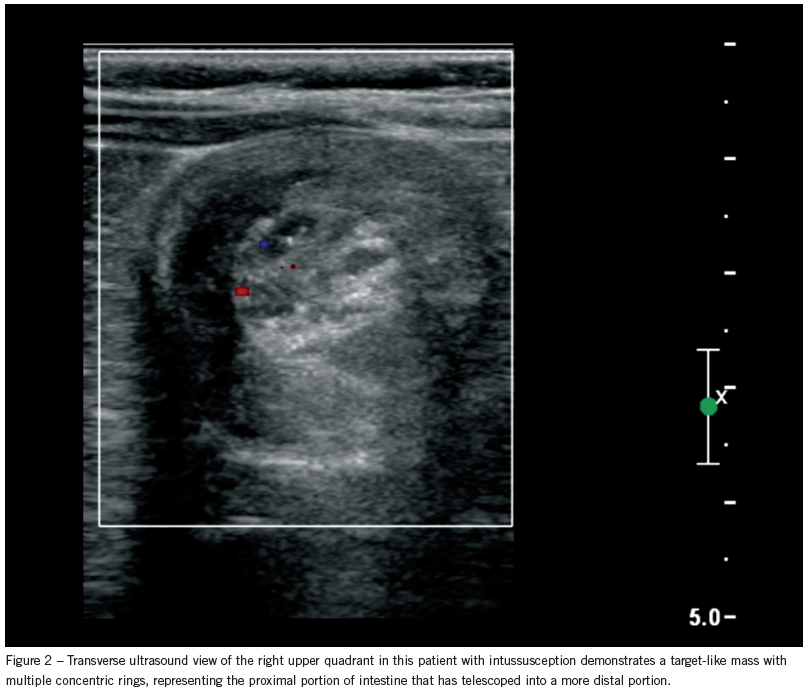

Further workup. Abdominal ultrasonography shows intussusception, which is easily reduced with an air enema (Figure 2).

Outcome of this case. The patient is admitted and observed overnight with no complications or recurrence of the

intussusception.

Intussusception. In patients with intussusception, one segment of intestine with its mesentery telescopes into a more distal segment. The most common site is at the ileocecal junction (termed ileocolic intussusception). The blood supply in the mesentery is compromised, leading to venous and lymphatic congestion, intestinal edema and, ultimately, ischemia with perforation and peritonitis.

Ultrasonography is the method of choice to detect intussusception at many institutions. It is most sensitive (98% to 100%) in expert hands, but the results are operator dependent. The classic finding is a “bull’s eye” or “coiled spring” lesion, which represents intestine within intestine. Ultrasonography can identify rare ileoileal intussusception and a pathologic lead point if one is present. Doppler ultrasonography may differentiate cases that cannot be reduced with enema (ie, those cases in which a lack of perfusion indicates bowel ischemia).